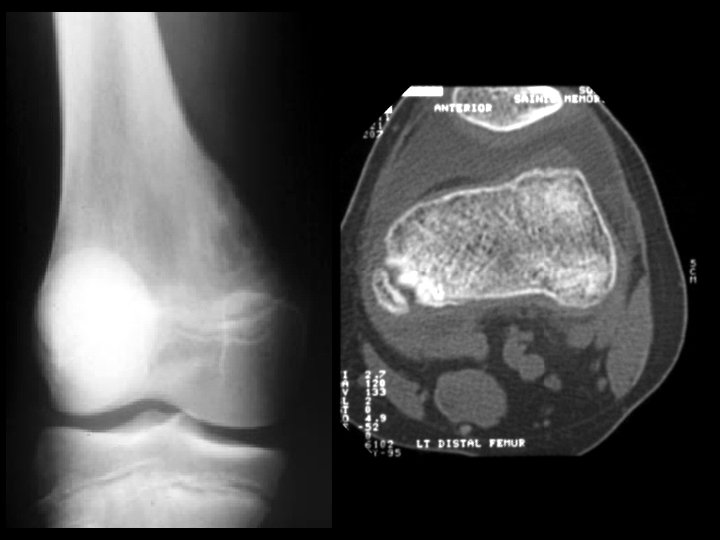

Tug lesion (avulsion injury) • Findings: – Cortical thickening and irregularity along the posterior medial distal femur – CT is diagnostic • ddx: – parosteal osteosarcoma – myositis ossificans

Cortical desmoid • Findings: – Irregular cortical thickening of the posterior (medial) distal femur – Avulsion injury related to the medial gastrocnemius • ddx: – Parosteal osteosarcoma – Myositis ossificans